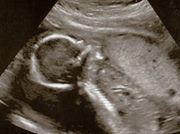

“Yeah, she said she just can't wait for you and Daddy to get to heaven."...From that moment on, the wound from one of the most painful episodes in our lives, losing a child we had wanted very much, began to heal.”